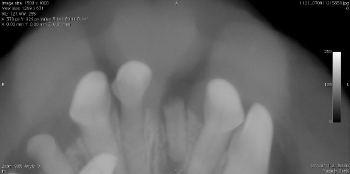

ポータブルレントゲンによる術中写真

術後の写真 充填( 赤ラインは根先部 )

麻酔なしのレントゲンにおいては2本が重なり一本に見えることもあります。